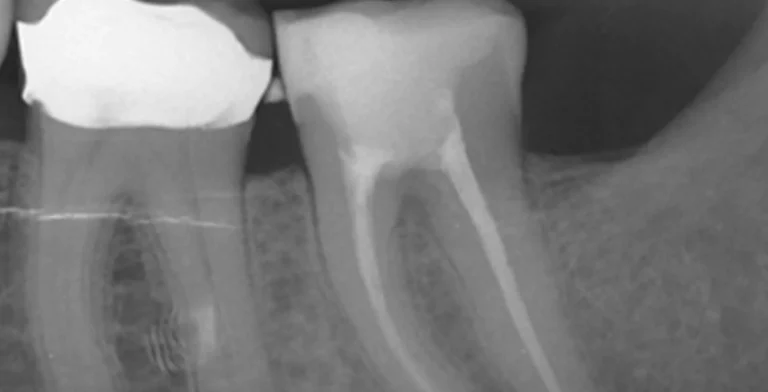

endo-ba04-before-treatment-vitrin-clinic endo-ba04-after-treatment-vitrin-clinic

endo-ba03-before-treatment-vitrin-clinic endo-ba03-after-treatment-vitrin-clinic

endo-ba02-after-treatment-vitrin-clinic endo-ba02-before-treatment-vitrin-clinic

endo-ba01-after-treatment-vitrin-clinic endo-ba01-before-treatment-vitrin-clinic